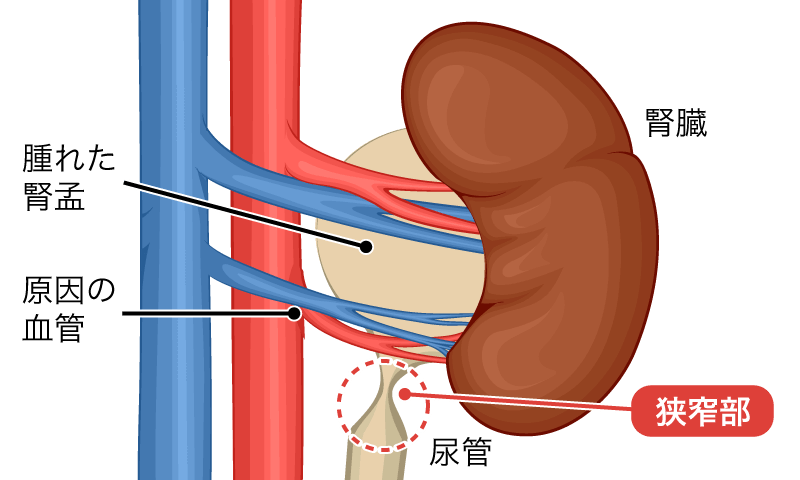

各尿管の上部は、腎臓の中央、腎盂として知られる領域にあります。尿は腎盂に集まり、尿管を通って膀胱に排出されます。

腎盂と尿管には、移行細胞と呼ばれる特定の種類の細胞が並んでいます。これらの細胞は、バラバラになることなく曲げたり伸ばしたりすることができます。移行細胞で発生するがんは、腎盂および尿管で発生する最も一般的な種類のがんです。